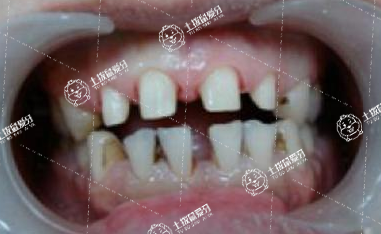

在這個(gè)愛美的時(shí)代,很多人在出現(xiàn)牙齒畸形后,往往就會(huì)變得越發(fā)不自信,長(zhǎng)此以往的話,還會(huì)進(jìn)一步影響牙友們的正常生活跟工作,當(dāng)牙友們?cè)谂R床上如果有牙齒擁擠或者畸形情況的話,往往還會(huì)給牙友們的正常生活帶來很大的影響,牙列擁擠多久能矯正好?接下來,我們一起來了解一下。

牙列擁擠的治療時(shí)間主要取決于牙列擁擠的程度和所采用的矯正方法。輕度和中度擁擠,治療方法主要是擴(kuò)大牙弓或?qū)ρ例X進(jìn)行鄰近小面切割以獲得間隙,治療時(shí)間相對(duì)較短,通常為一年左右。嚴(yán)重?fù)頂D,例如8毫米以上的牙列擁擠,或伴有其他錯(cuò)畸形,如上下牙弓關(guān)系紊亂和與顱骨關(guān)系不協(xié)調(diào),需要拔牙或擴(kuò)弓甚至手術(shù)治療通常被用來共同解決這些錯(cuò)畸形,治療時(shí)間通常為2年甚至更長(zhǎng)。

牙列擁擠矯正需要1年-3年的時(shí)間。牙列擁擠的如超過8毫米牙頜畸形,或伴隨其他的牙齒,例如,上下牙弓的障礙之間的關(guān)系,以及與頭骨的關(guān)系不和諧,通常采用拔牙弓或臨床擴(kuò)張,甚至手術(shù)治療方法,解決這些錯(cuò)頜畸形,連同所有的時(shí)間在2年或更長(zhǎng)的時(shí)間。